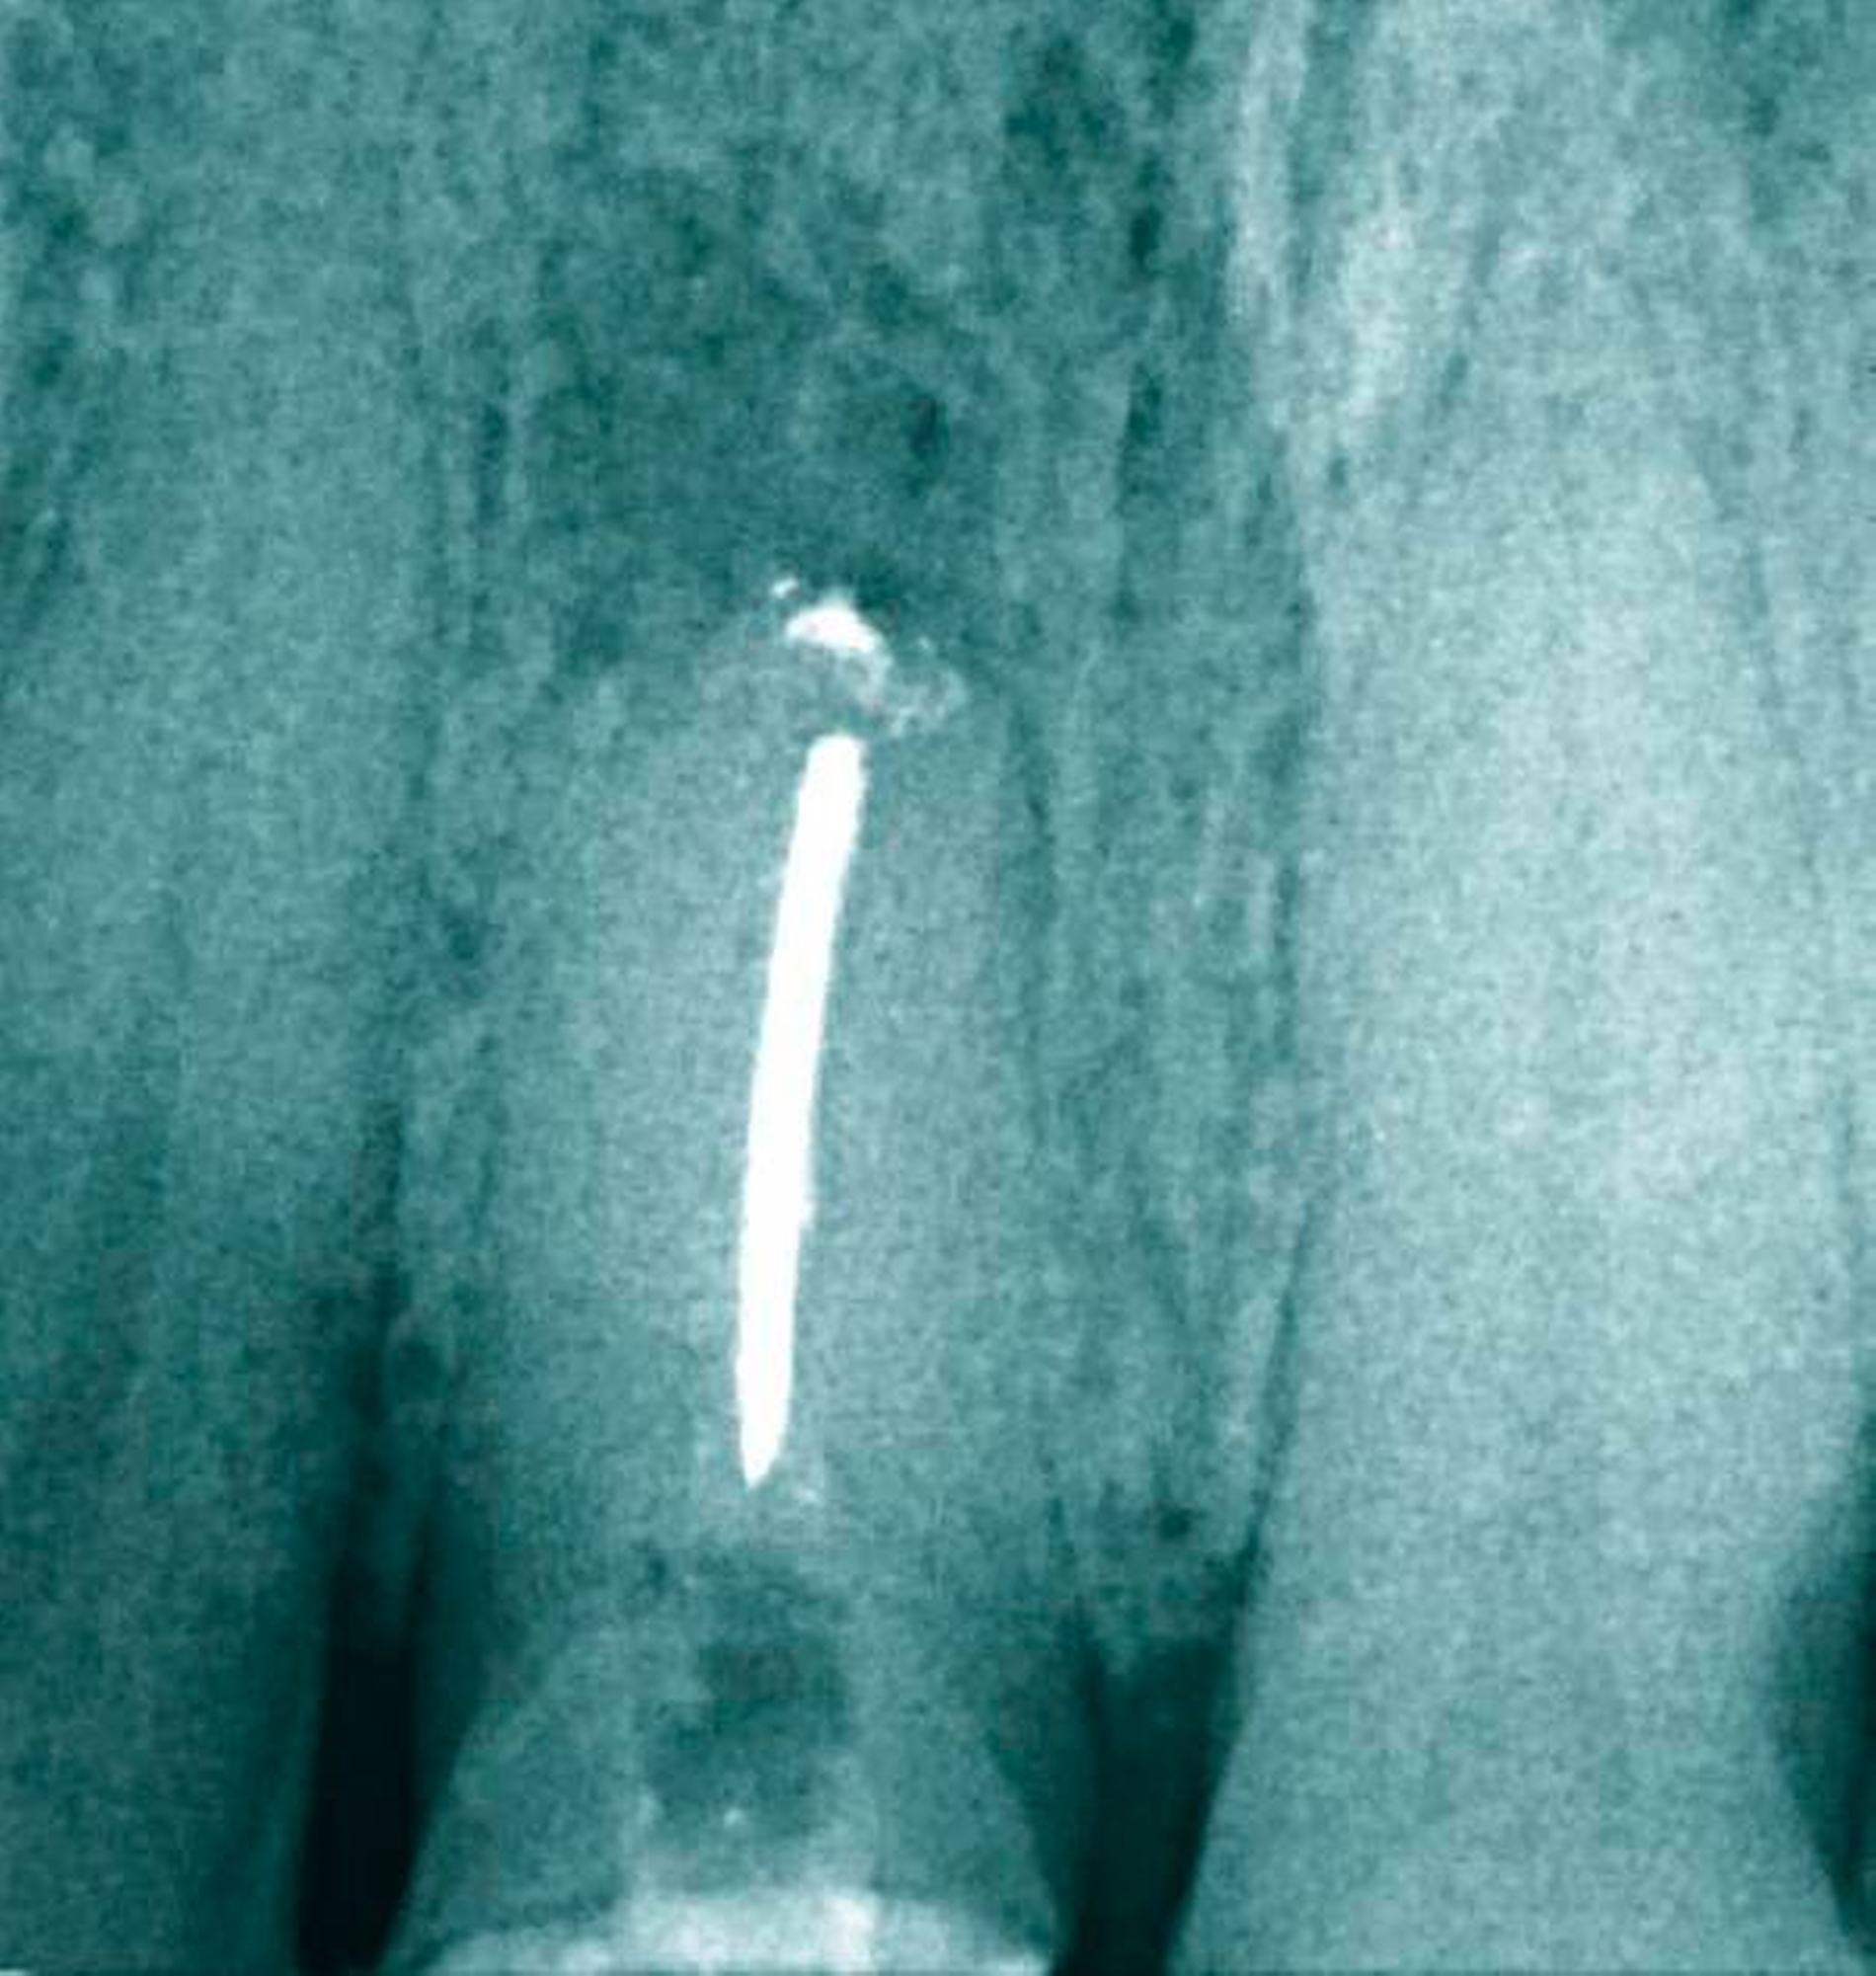

Ein Patient wurde zur Wurzelkanalrevision an Zahn 11 vor einer geplanten prothetischen Versorgung überwiesen. Zum Zeitpunkt der Überweisung lag keine klinische Symptomatik vor. Das vom Patienten mitgebrachte Röntgenbild zeigte eine bereits resezierte Wurzel, die mit einem Silberstift gefüllt war und eine apikale Läsion aufwies (Abbildung 16). Beim ersten Termin wurde nach Isolation des Zahnes mit Kofferdam der Silberstift dargestellt (Abbildung 17) und mittels Ultraschall entfernt. Die Desinfektion und Reinigung erfolgte mit NaOCl und EDTA. Die endometrische Längenmessung ergab 20,5 mm mit einer initialen Anfangsfeile von ISO 70. Eine Messaufnahme wurde angefertigt (Abbildung 18). Schließlich erfolgte eine Einlage mit Kalziumhydroxid. In der zweiten Sitzung wurde nach erneuter ausgiebiger Spülung und mechanischer Präparation mit Handinstrumenten bis ISO 80 und Ultraschall die Arbeitslänge noch einmal mittels Papierspitzenmessung verifiziert (Abbildung 19). Anschließend wurden ein apikaler Plug mit Total Fill BC Root Repair Material appliziert (Abbildung 20) und eine Röntgenaufnahme angefertigt (Abbildung 21). Ein Glasfaserstift wurde inseriert und der Zahn mit einem dual-härtendem Komposit verschlossen (Abbildung 22).